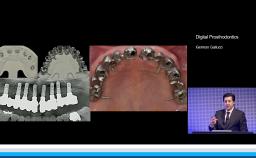

German Gallucci